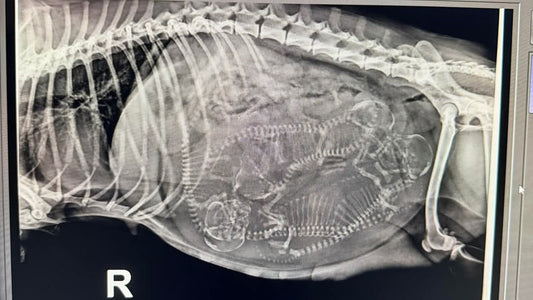

How Ultrasound and X-Ray Are Used During Canine Pregnancy

Learn how ultrasound and x-ray are used during dog pregnancy, what each test shows, and when breeders should use them.